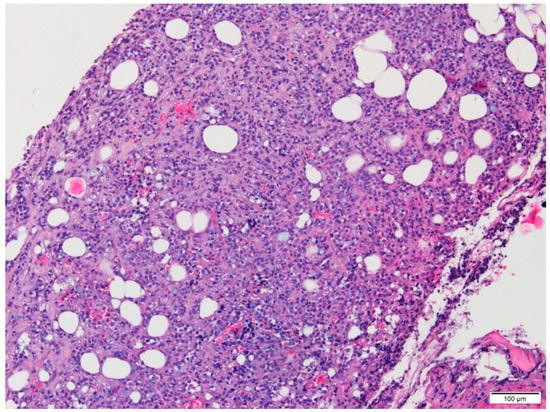

Microscopic examination of conventional stained slides revealed breast biopsy fragments with chronic inflammatory infiltrates, predominantly lymphocytic, with rare plasma cells, organized in groups around ductal–acinar structures, blood vessels and diffusely dispersed in the interstitium. One of the fragments presented massive tumoral infiltration (Figure 1), histopathologically consistent with invasive lobular carcinoma growing in solid nests and sheets with marginal single files of discohesive, equidistant cells, some of them with cytoplasmic microlumina, in a reduced sclerohyaline stroma with diffuse lymphocytic infiltrate. The tumoral infiltration was categorized as moderately differentiated (G2 histological grade) corresponding to a Nottingham score of 7: no duct formation (Df = 3 points), marked nuclear pleomorphism (A = 3 points) with occasional plasmacytoid marginal cells and rare mitotic figures (3/10 high power fields at 40×/0.45) (M = 1 point). Tumoral necrosis was not identified. No in situ component was present. Tumor emboli were not detected. Perineural invasion could not be determined because no resting nervous structures were identified.

Figure 1.

Conventional aspect of the lesion infiltrating adipose tissue (HE, 10×).